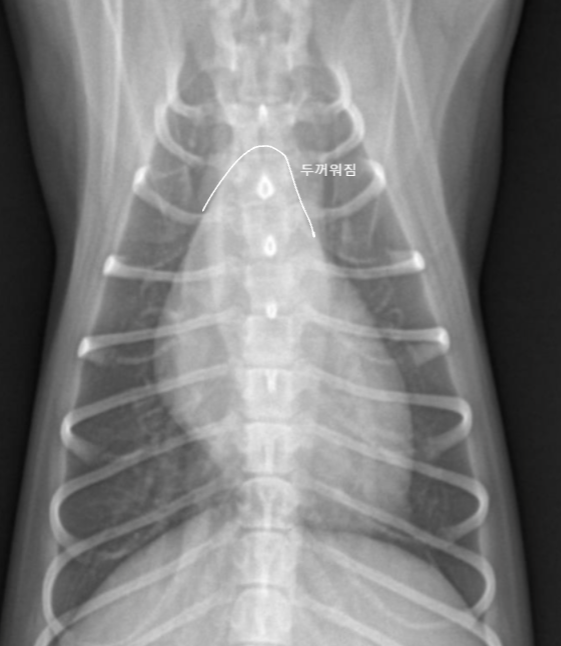

| VHS | Vertebral heart score.![]() | ์ฌ์ฅ ํฌ๊ธฐ์ ์ฒ์ถ๋ผ์ ๋น๊ต. - ์ฅ์ถ : carina์ ventral border์์ ์ฌ์ฅ์ apex๊น์ง (fat ํฌํจํ๋ฉด ์ ๋จ) - ๋จ์ถ : ์ฅ์ถ๊ณผ ์์งํ๊ฒ, CVC ๊ทผ์ฒ์์ ๊ฐ์ฅ ๋์ ๋ฒ์ โ T4 ๋งจ ์์ชฝ๋ถํฐ ์ฅ์ถ/๋จ์ถ ๊ธธ์ด๋งํผ ๊ฐ์ ๋ ์ฒ์ถ๋ผ์ ๊ฐ์๋ฅผ ๋ํจ. Dog : 8.5 Cat : 6.7 |